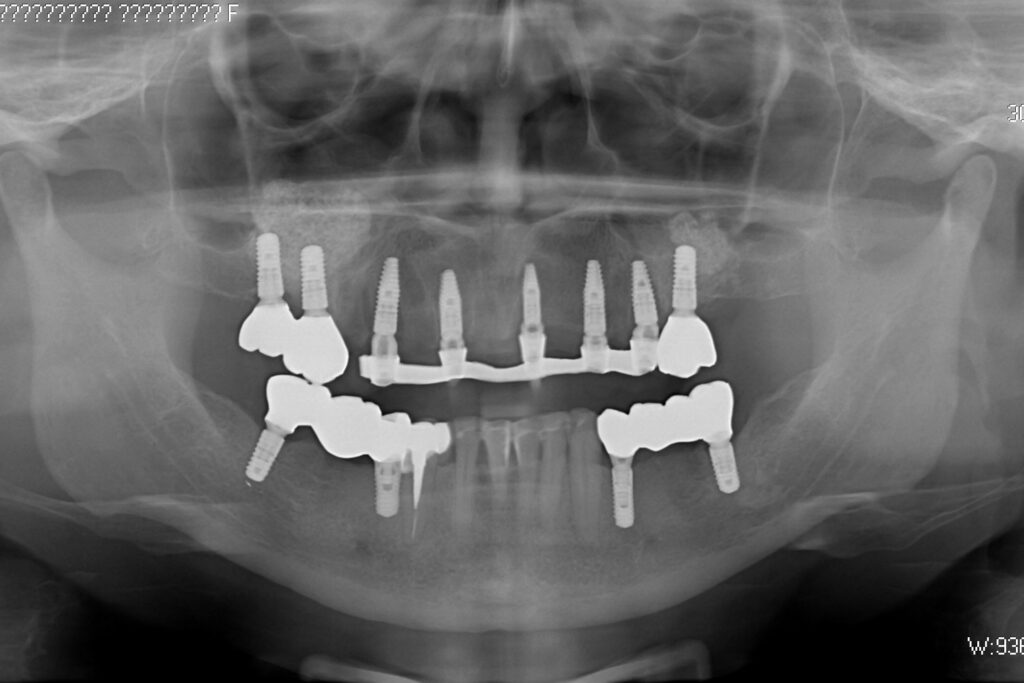

Процесс работы

Что было сделано:

На верхней челюсти были сняты старые мостовидные протезы и удалены зубы, которые находились в неудовлетворительном состоянии.

Установлены 5 имплантантов Straumann BLT и сняты оттиски. Спустя 6 дней на верхней челюсти зафиксирован протез из пластмассы, армированный металлической балкой с опорой на 5 дентальных имплантатов. Ранее у пациента уже были установлены 3 имплантата Straumann.

При постоянном протезировании протез будет зафиксирован на 8ми имплантатах.